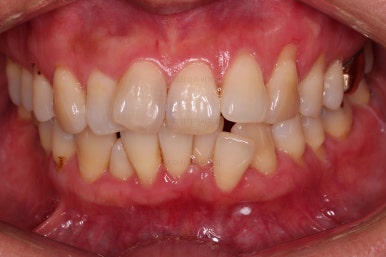

동래임플란트교정 초진 시 입안의 모습입니다.

치열이 전반적으로 삐뚤어져 있는 양상이고요.

아랫니가 윗니보다 더 많이 삐뚤어 있는데요.

비밀은 바로 화살표에 있습니다.

유치 잔존

말그대로 어릴 때 빠져야 할 유치가 남아있다는 뜻인데요.

앞니 사이에 뾰족하게 남아있다 보니 자리만 많이 차지하고 있는 모습이었고 다른 영구치를 더 삐뚤게 만들었어요.

딱히 영구치가 모자라진 않는데 유치가 잔존하는 굉장히 드물고 독특한 상황이었습니다.

당연히 유치는 뽑기로 했고요.